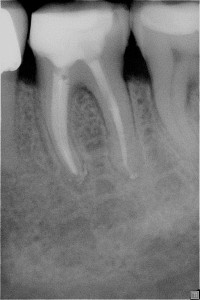

Fallbeispiel-2_Bild_4_Pat_781_Za_36_R__ntgenkontrolle_n_Stift Posted on 5. Februar 201615. Februar 2016 by Administrator